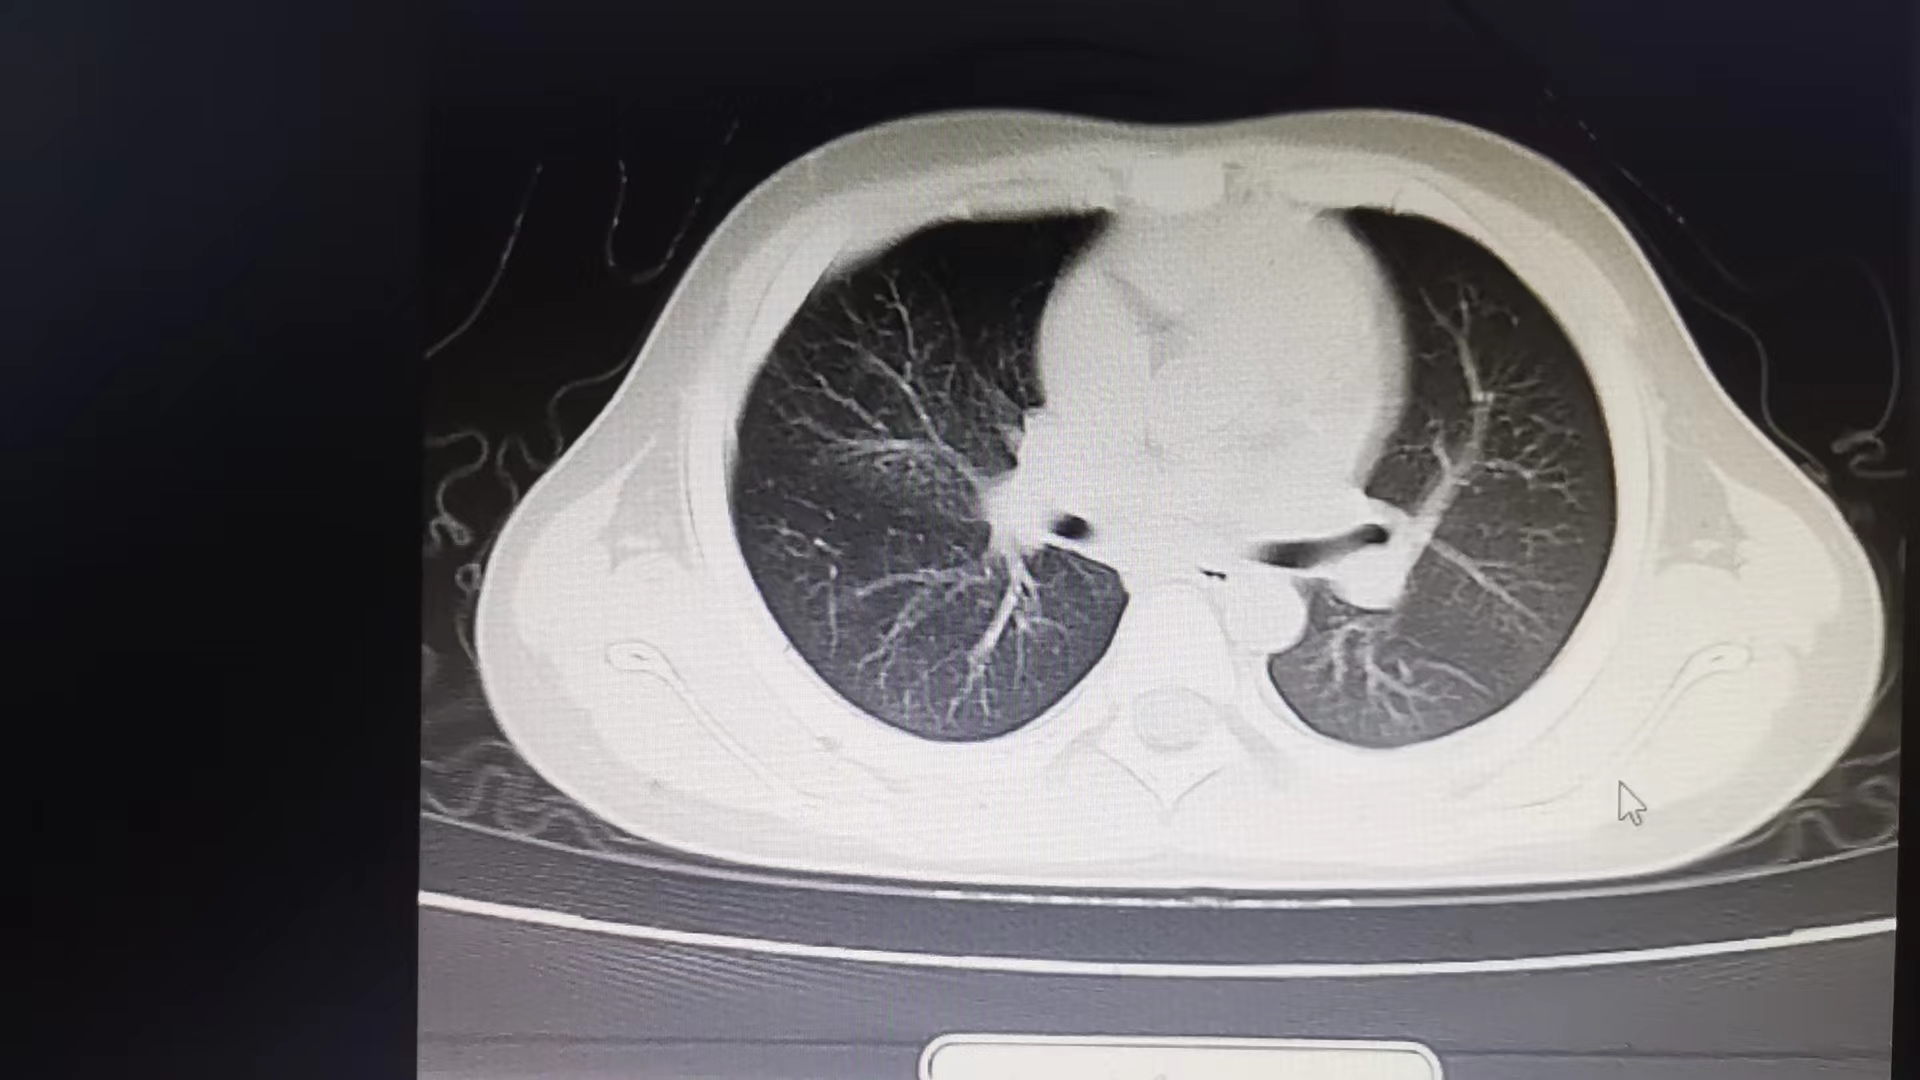

患儿陈某,咳嗽发热3天后到娄底市第二人民医院儿科就诊,经诊断,为右下肺大叶性肺炎。大叶性肺炎发病比较急骤,如果不及时治疗可能引起肺外感染或出现全身中毒症状。该科立即予以抗感染,化痰平喘及雾化治疗配合儿科特色中药肺炎敷贴,治疗6天后复查明显好转,再行巩固治疗后症状消失,肺部呼吸音恢复正常出院。

大叶性肺炎患者治疗6天后肺部CT